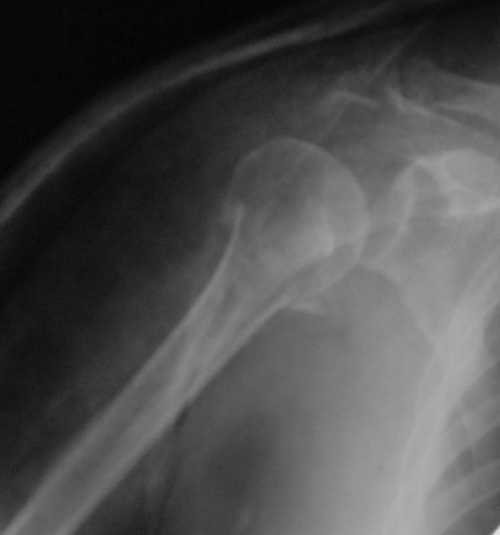

Re: Оскольчатый перелом шейки, головки плечевой ко

Снимки на 1-е сутки после репозиции и на 8- сутки после репозиции.